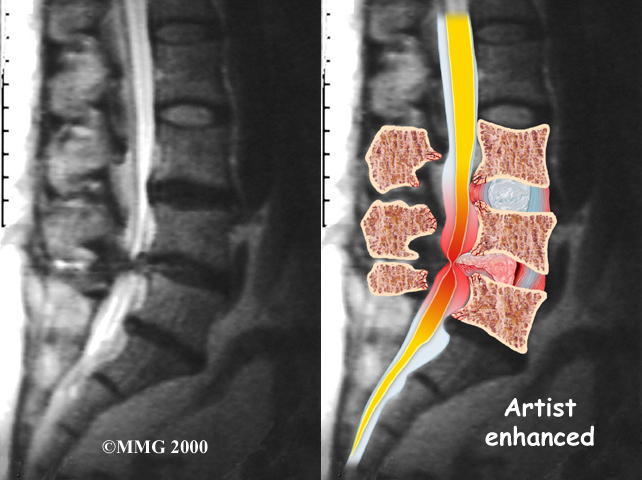

The best way to see the effects and extent of lumbar spinal stenosis is with a magnetic resonance imaging (MRI) scan. The MRI machine uses magnetic waves rather than X-rays to show the soft tissues of the body. This test gives a clear picture of the spinal canal and whether the nerves inside are being squeezed. This machine creates pictures that look like slices of the area your doctor is interested in. The test does not require dye or a needle.